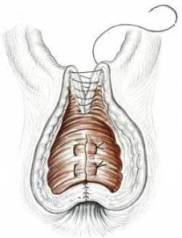

Liegt ein anatomischer Defekt des Schliessmuskels (Sphinkter) im Sinne einer Zerreissung des Sphinkters vor, ist die Sphinkterrekonstruktion (Sphincterrepair) die Operation der Wahl. Nach endosonographischer Diagnostik des muskulären Defekts wird dieser operativ dargestellt und vernäht.